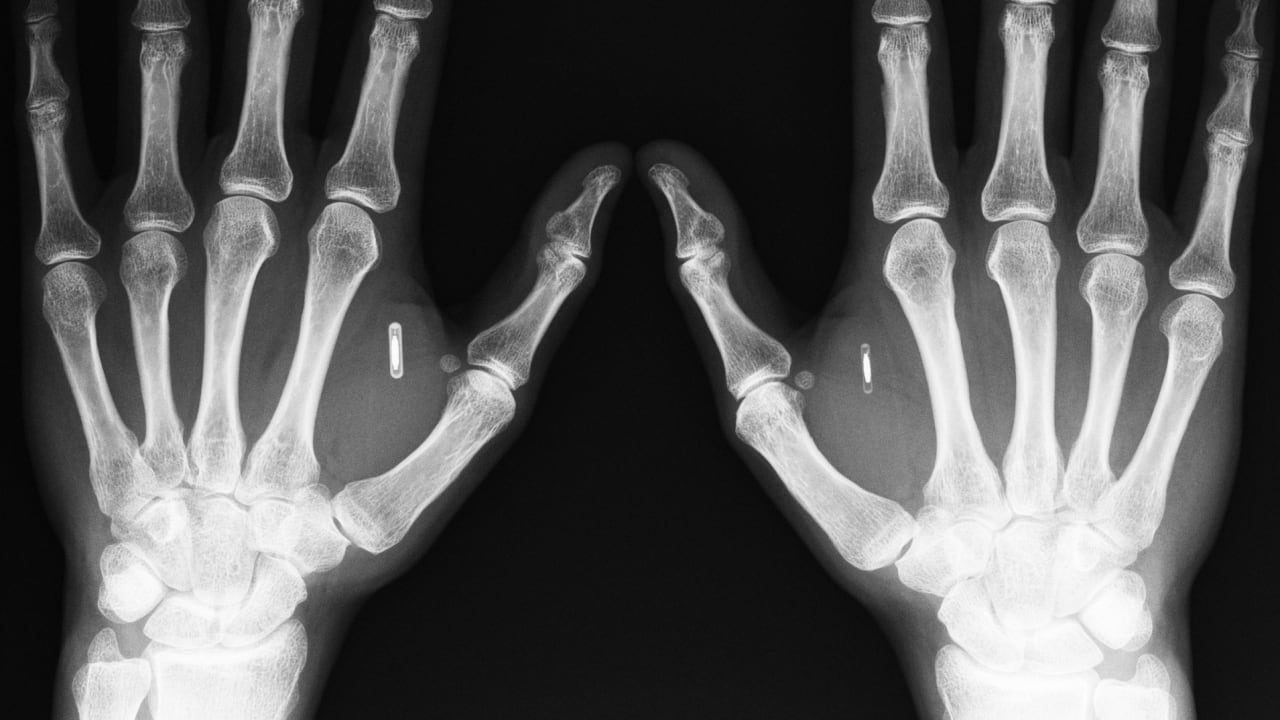

Magnets Under Skin . magnets and metals stick to human skin. If it's metal and hidden underneath the skin, doctors might be able to use an. got something stuck in your arm? software engineer miana windall has about 25 implants under her skin, ranging from magnets to rfid tech. quite a few biohackers have magnets implanted in their fingers. when i first got it, i wasn’t disappointed. Magnetic field therapy uses different kinds of magnets on the body to help boost your overall health. Nestled just beneath my skin, the magnet tugged and tickled when it got close. If it's metal and hidden underneath the skin, doctors might be able. These can be excited by small coils of wire linked to external sensors such as. 2 min read. Got something stuck in your arm? And yet, there are copious examples, including a significant number.

Magnets Under Skin These can be excited by small coils of wire linked to external sensors such as. software engineer miana windall has about 25 implants under her skin, ranging from magnets to rfid tech. when i first got it, i wasn’t disappointed. Got something stuck in your arm? quite a few biohackers have magnets implanted in their fingers. magnets and metals stick to human skin. These can be excited by small coils of wire linked to external sensors such as. If it's metal and hidden underneath the skin, doctors might be able. And yet, there are copious examples, including a significant number. Magnetic field therapy uses different kinds of magnets on the body to help boost your overall health. Nestled just beneath my skin, the magnet tugged and tickled when it got close. 2 min read. got something stuck in your arm? If it's metal and hidden underneath the skin, doctors might be able to use an.